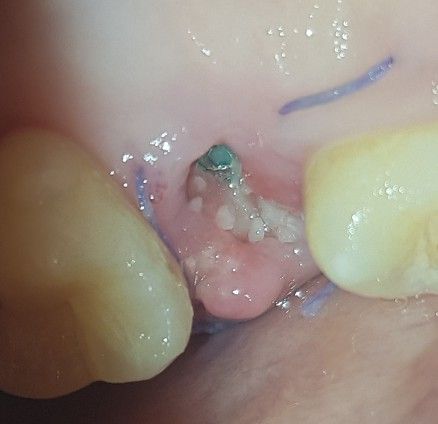

20대 임플란트 나사 식립 부위가 이상해요 원래 이런건가요

신경치료 후 크라운 씌웠던 치아에 염증이 생겨 발치하고 뼈이식 후 당일 나사 식립까지 마쳤습니다.

24번 치아구요..(좌상악)

수술한지 10일째입니다. 수술 직후부터 수술 부위에 노스르슴하기도 하고 희뿌연 거품이 생겼었는데 대수롭지 않게 생각했어요.

그러다가 9일째인 어제 사진을 찍었는데 거품 때문에 사진에 잘 안보이길래 가글 한번 하고 찍었습니다.

근데 뼛가루가 막...엄청 많더라구요 ㅠㅠ 이게 원래 이럴 수 있는건가요? 명절이라 치과가 영업을 안해서 여기에 여쭙습니다 ㅠㅠ

해당 사진으로 보아서는 크게 문제가 되지 않을 것으로 보입니다. 임플란트 술식을 할 때 뼈이식을 같이 한 것으로 보이며 상부에 남아 있는 뼈가 노출되었거나 기존의 뼈와 융합되지 못하고 탈락한 뼈이식재가 나온 것으로 보입니다. 잇몸 자체에 발적이나 부종 등이 없으므로 큰 문제는 없을 것으로 보이나 x-ray를 한 번 촬영하는 것은 도움이 될 것으로 보입니다.

뼈이식을 같이 하신거 같은데 뼈가루가 조금씩 나오는건 크게 상관없습니다. 너무 걱정은 하지 마시고 치과에 가셔서 엑스레이 사진을 찍어보시면될것같습니다.